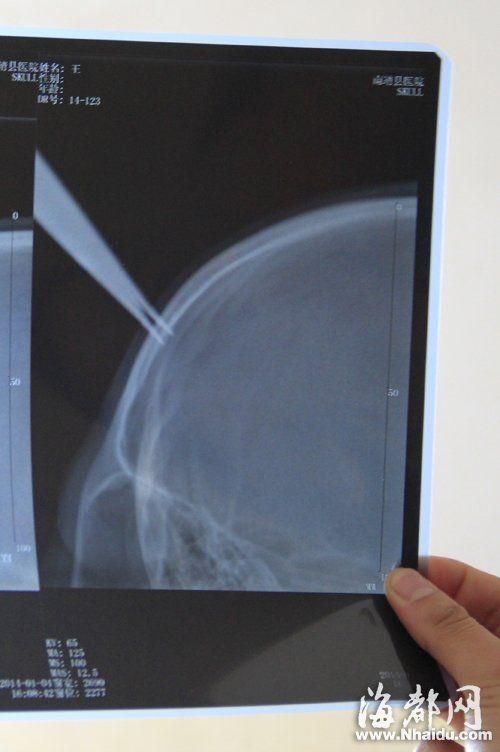

小女孩的X光照,剪刀刺进女孩的颅骨内

小女孩的主治医生介绍,当晚,他们给女孩做了手术,顺利摘除剪刀,术中发现剪刀刺入女孩颅骨内,所幸没有刺破她的颅内硬脑膜,女孩没有生命危险。目前,女孩康复情况良好,预计再观察治疗几天就能出院。 (海峡都市报记者 林深圳 戴江海 通讯员 林智敏 文/图)